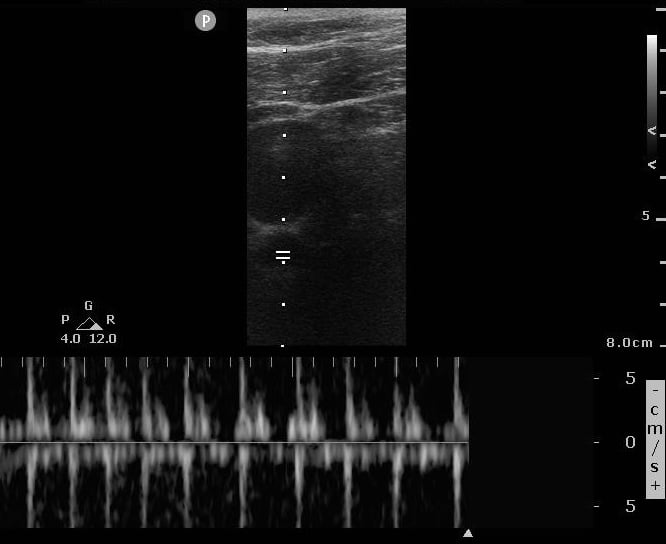

Case 1, Image 1.

Pulse wave Doppler started during ongoing compressions (with high amplitude tracings that alias). Image courtesy of Yale School of Medicine, Emergency Department.